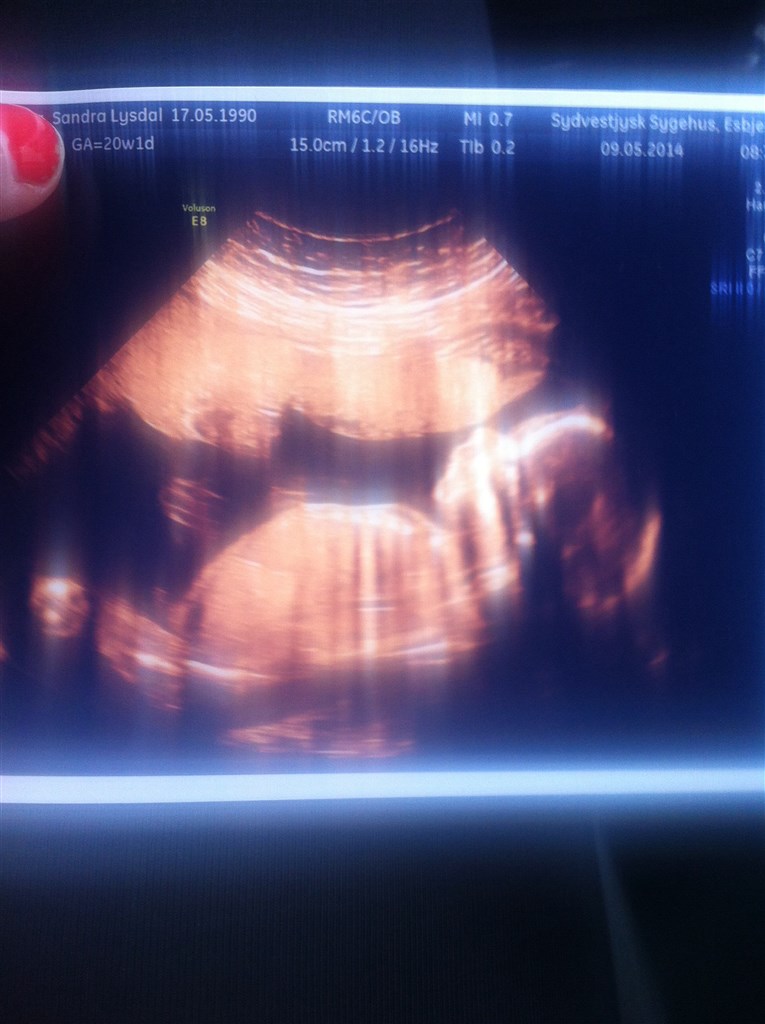

DRENG

Er bare så glad, glæder mig til at fortælle Lukas at han skal have en lille bror

jeg havde det også på fornemmelsen at det var en dreng igen

er lykkelig over at han var perfekt ...

Yes .. Elsker mine drenge ...